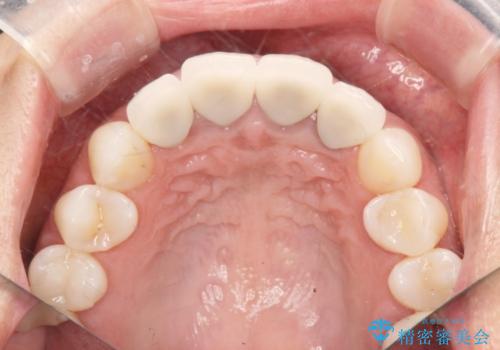

一見して問題ないように見える左側の2前歯は、セラミックを除去してみると亀裂や虫歯の再発が見られました。

抜歯時に可及的に歯肉のボリュームを保つよう骨充填材とコラーゲン製剤による填塞を行い審美的かつ機能的なブリッジとなるよう治療を進めます。

- 66万円(ジルコニアクラウン×5・仮歯×5)費用は治療当時の料金となります